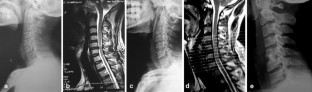

Fig. 1

Fig. 2

Fig. 3